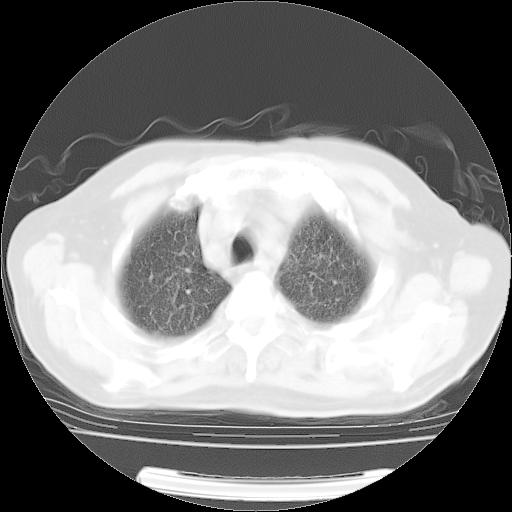

4月14日肺部CT

23.JPG

24.JPG

25.JPG

26.JPG

肺部CT平扫未见异常。